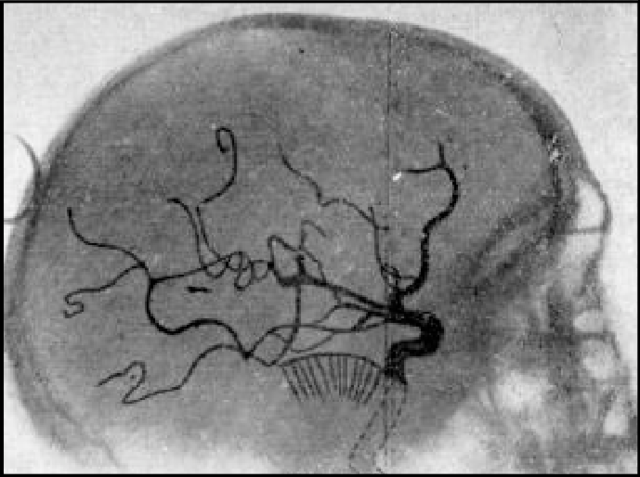

• Primera angiografía.

Primera angiografía.

Por António Egas Moniz.